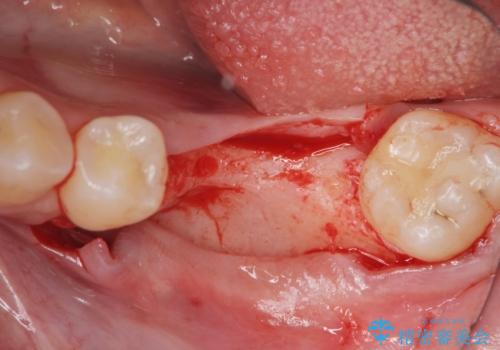

- 他院で抜歯後放置してしまった左下の奥歯の機能・見た目の回復を希望され来院されました。

放置したことによる影響か骨が吸収し、インプラント周囲に十分な骨が確保できないような状況であったため骨造成を併用したインプラント治療を計画します。